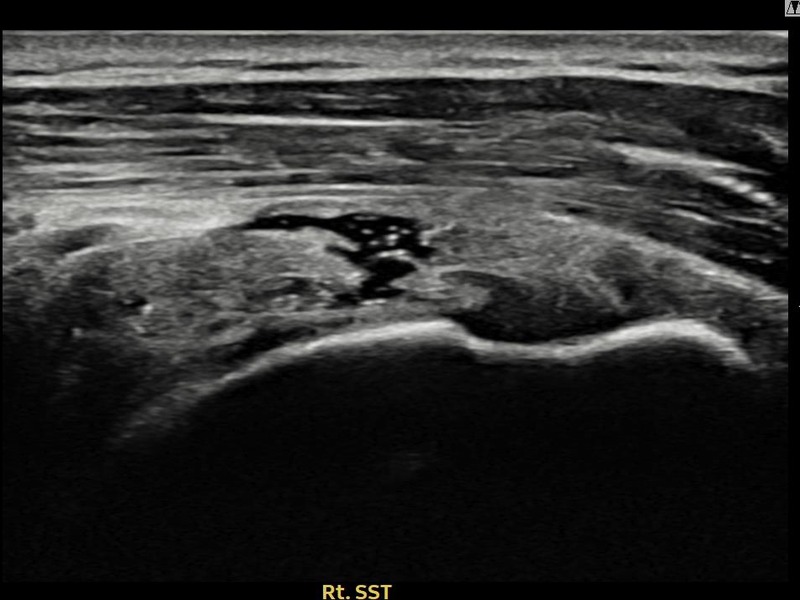

김ㅇㅇ님 · 우측 극상근건 관절면측 부분파열

우측 어깨 통증이 일상 동작에서 지속되어 내원하셨습니다. 초음파 검사에서 극상근건 관절면측 부분파열 확인 후 축소봉합술을 시행하였고 구조적 회복이 이루어졌습니다.

상세 보기 →